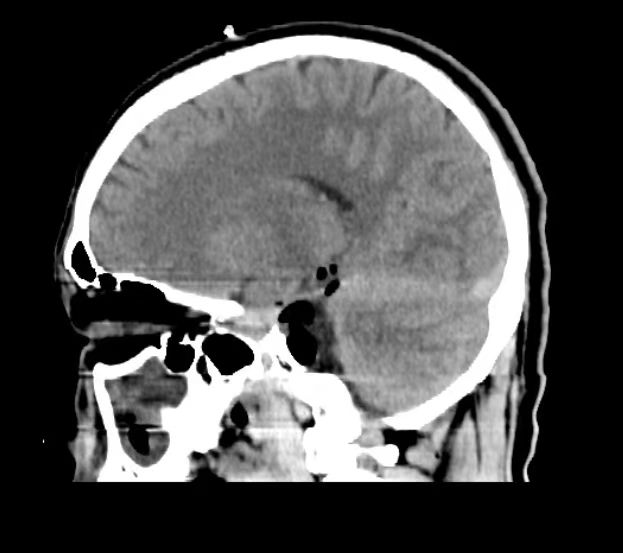

在郝少才主任医师团队全面、专业的准备下,李先生在完成了“血腥三角”巨大肿瘤切除,手术中全程无牵拉操作,使用神经内镜和显微镜双镜联合下神经电生理监测,手术中肿瘤全切,面听神经得到了保留,无面瘫,听力保留完好、无下降,术后患者恢复良好,术后病理证实胆脂瘤,属于良性肿瘤。患者及家属表示非常满意。

▲术后CT提示肿瘤完整切除